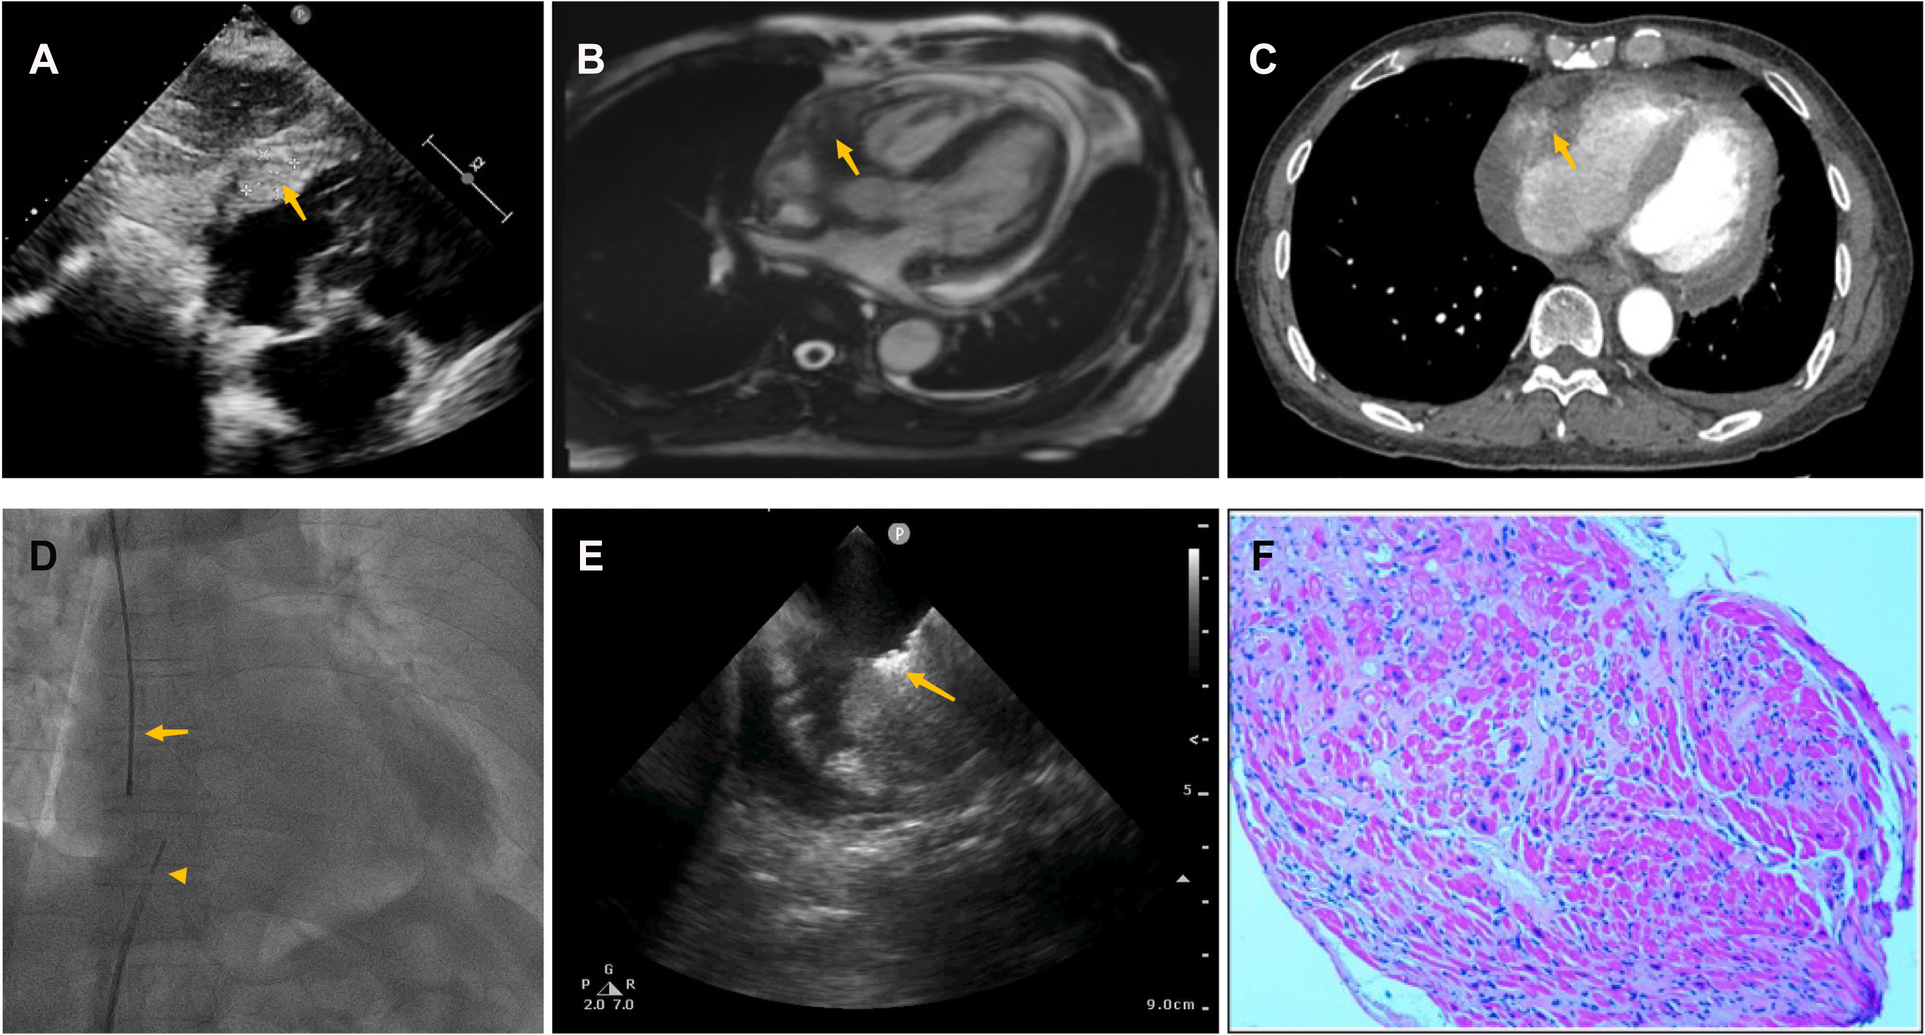

Case3

A 62-year-old man was transferred from local hospital to our cardiology department for chest tightness and recurrent pericardial effusion for two months. More than two months ago, the patient experienced chest tightness. When the patient went to the local hospital's emergency room, chest CT showed enlarged cardiac shadow and massive pericardial effusion with interstitial pulmonary edema in the lower lobe of right lung.

Pericardiocentesis was used to treat his bloody pericardial effusion and drain it. In order to treat the symptoms, diuretics and antihypertensives were given. After one month, the patient once more experienced a significant increase in pericardial effusion along with obvious chest tightness. The patient then went to the emergency department for pericardial effusion drainage. Unexpectedly, his chest tightness and dyspnea immediately got worse. He was admitted to our hospital for further diagnosis. A second pericardiocentesis was carried out, producing 900 ml of bloody fluid in total. Blood tests performed shortly after admission revealed high levels of the C-reactive protein (CRP) (25.4 mg/L), pro-Brain natriuretic peptide (660 pg/ml), D-dimer (3,560 ug/L), and tumor marker CA125 (87 U/ml). Echocardiography showed a hyperechoic mass at the right ventricle lateral wall junction (Figure 5A). Enhanced-CMR and chest CT clearly confirmed that a mass (38mm × 23 mm) was located at the junction of the right atrium and ventricle and had a modest amount of pericardial effusion (Figures 5B,C). Pathological analysis of the pericardial effusion revealed sporadic mesothelial cells and inflammatory cells but no tumor cells. For further diagnosis, we carried out an atrial biopsy under the guidance of the ICE (Supplementary Appendix Videos S5–6). The biopsy technique was the same as above without complications (Figure 5D,E). This result revealed small vascular lumen formed by single cell (Figure 5F). and considered as an intermediate or low-grade malignant vascular tumor with positive CD34, CD31, Fli-1, and ERG expression, confirming the diagnosis of cardiac epithelioid hemangioendothelioma (EHE). With the pericardial effusion's rapid progression and significant dyspnea, the patient eventually discontinued getting treatment.

Figure 5

Multiple investigations for diagnosis of Case3. (A) Transthoracic echocardiography showed cardiac mass lesion (arrow) in the RA. (B) Chest enhanced CT, and (C) Cardiac enhanced-MRI revealed a large mass (arrow) at the junction of the RA and RV. (D) Catheter for intracardiac echocardiography (arrowhead) and cardiac bioptome (arrow). (E) The intracardial echocardiography demonstrates well-targeted biopsy catheter (arrow) on the mass. (F) Histopathological imaging revealed small vascular lumen formed by single cell, and cardiac epithelioid hemangioendothelioma (EHE) was diagnosed.